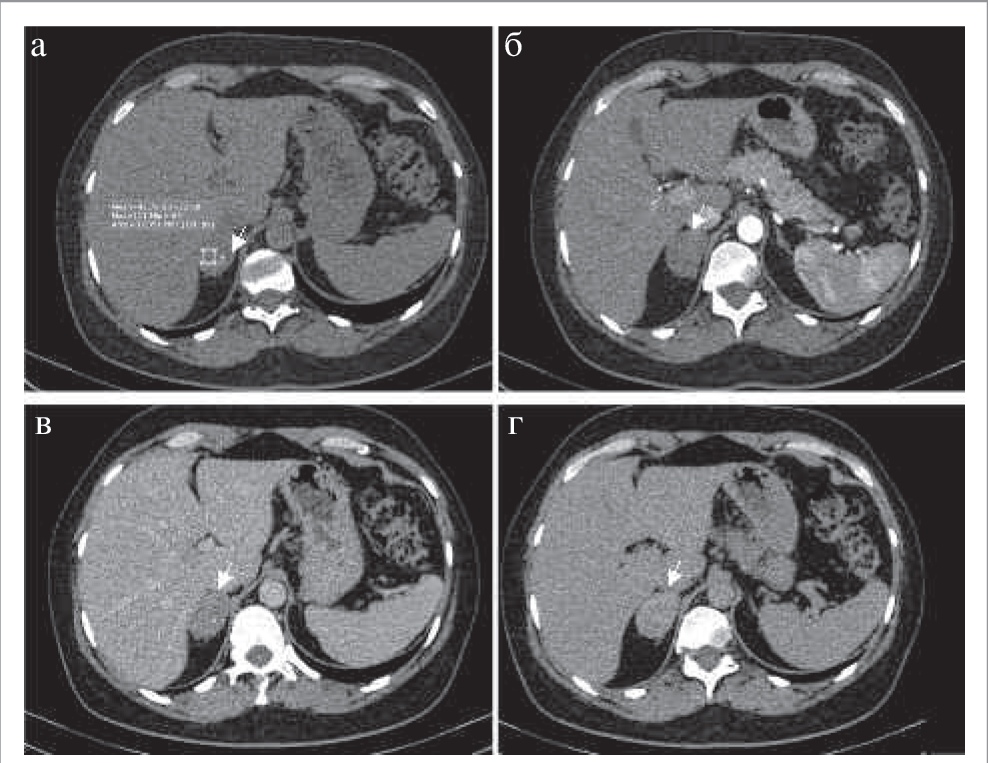

На КТ-изображениях аденомы обычно представляют собой образования с четкими ровными контурами овальной формы, однородной структуры, размером, как правило, менее 3 см. При динамическом наблюдении размер аденом не меняется или увеличивается в пределах нескольких миллиметров в год (рис. 2) [5].

Рис. 2. МСКТ, аксиальная проекция: а – НФ; б – АФ; в – ВФ; г – ОФ. Аденома надпочечника с низким содержанием жира (стрелка). Примечание. МСКТ – мультиспиральная компьютерная томография.

В зависимости от количества внутриклеточных жировых включений различают аденомы с высоким содержанием жира (80%) и с низким его содержанием (20%), что проявляется характерной КТ-картиной [7]. Так, аденомы с высоким содержанием жира представлены образованиями плотностью на нативных изображениях до 10–15 ед. Н.

Все аденомы имеют патогномоничное накопление контрастного препарата с быстрым «вымыванием» его после внутривенного болюсного контрастирования, что позволяет дифференцировать аденомы с остальными заболеваниями надпочечников.

Для оценки характера контрастирования в большинстве случаев проводится четырехфазное КТ-сканирование с болюсным введением неионного йодсодержащего контрастного препарата со скоростью 2–4 мл/с, дозой контрастного вещества с концентрацией 300–350 мг йода/мл (60–76%) не менее 1 мл/кг веса тела пациента (лучше – 100–140 мл). Исследование проводят в нативную фазу (НФ), артериальную фазу – АФ (18–25 с после начала введения болюса контрастного препарата или 10 с после достижения пика 100–150 ед. Н на болюс-трекере), венозную фазу – ВФ (55–65 с от начала введения болюса) и отсроченную фазу – ОФ (15 мин после введения контрастного препарата). Для аденом максимальное накопление контрастного препарата в большинстве наблюдений определяется в ВФ. Впервые оценку характера вымывания контрастного препарата в ОФ на различных минутах (от 5 до 15-й) при образованиях надпочечников описали в своей работе M. Korobkin и соавт., где выявили, что наиболее точные результаты получены при измерении плотности образования в ОФ на 15-й минуте [1].